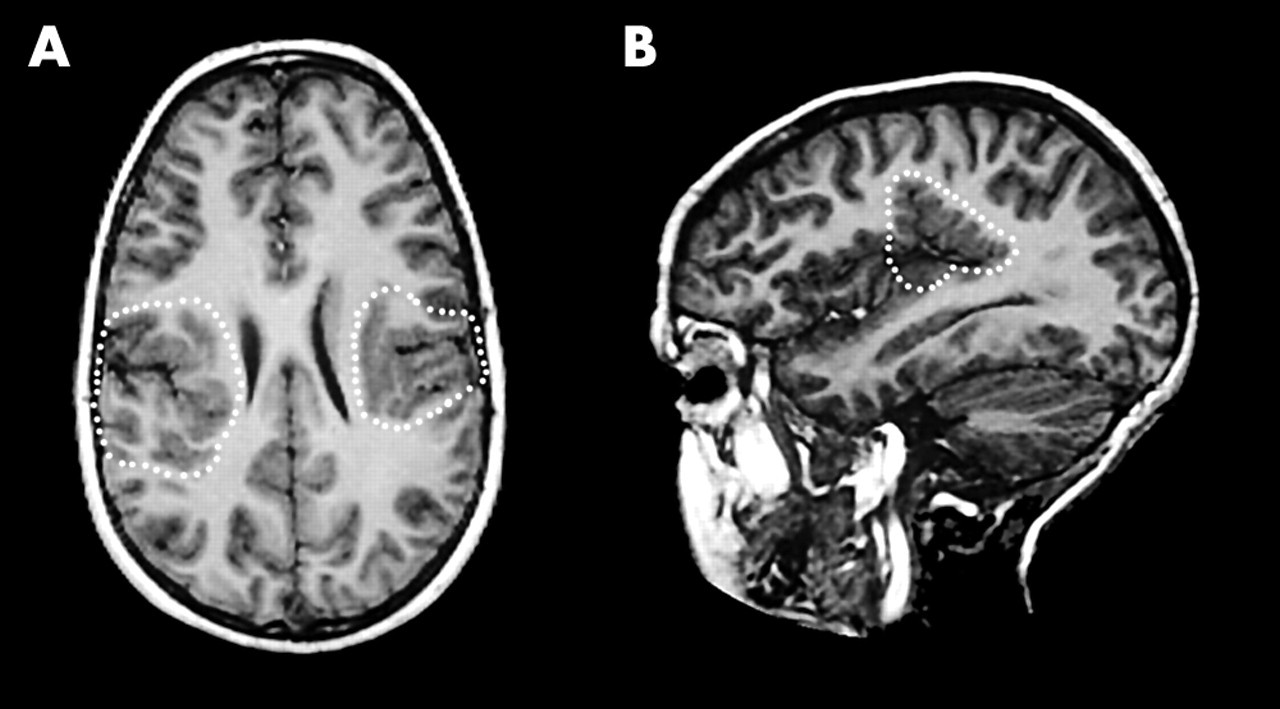

Cortical Heterotopias

Misplaced neural tissue.